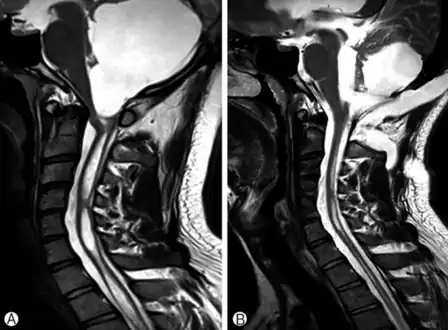

a)Large cystic mass at the posterior fossa with compression of the 4th ventricle b) postoperative MRI, a residual cyst and syringomyelia was decreased.